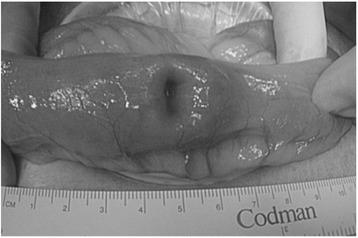

Isolated metachronous gastrointestinal metastases from advanced-stage lung cancer are rarely diagnosed on the basis of symptoms and resected. In this report, we present a case of resectable metachronous gallbladder and small intestinal metastases of lung cancer. An 86-year-old woman was treated for lung cancer with resection of the right inferior lobe. Five months after the surgery, she was re-admitted because of melena and anemia. Ultrasonography showed a gallbladder tumor with gastrointestinal hemorrhage, and laparoscopic-assisted cholecystectomy was subsequently performed. However, 2 months after this event, the patient presented again with melena and anemia and was diagnosed with a small intestinal tumor. Therefore, laparoscopic-assisted partial resection of the small intestine was performed. Immunohistochemical staining for thyroid transcription factor-1 and cytokeratin 7 confirmed that the two resected tumors were metachronous metastases of the primary lung cancer. The patient died of liver metastases 5 months after the last surgery. Our experience with this case suggests that surgical resection might not be curative but palliative for patients with isolated gallbladder and small intestinal metastases diagnosed on the basis of melena that is resistant to conservative treatment.